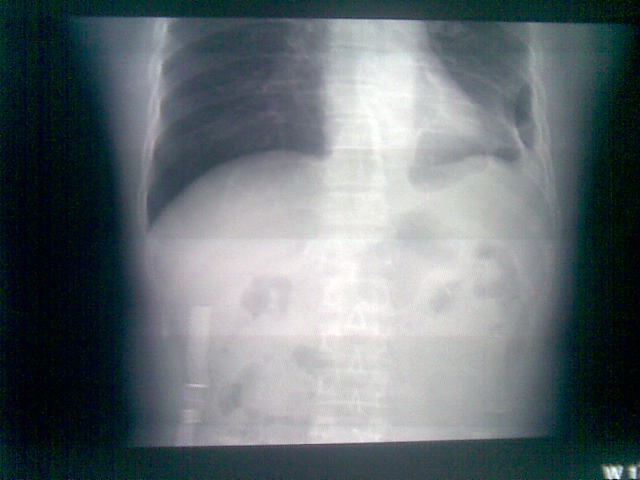

标题: CT23981:男,38岁阑尾炎术后透视胸腔积夜!做CT如下!积液包 [打印本页]

标题: CT23981:男,38岁阑尾炎术后透视胸腔积夜!做CT如下!积液包

可能与阑尾术后关系不太大,1.胸膜增厚粘连见少量气体。包裹脓气胸?左侧网膜囊脓肿?

.胸膜增厚粘连见少量气体。包裹脓气胸

少量积液部分粘连

左侧胸膜增厚、粘连+包裹液气胸。